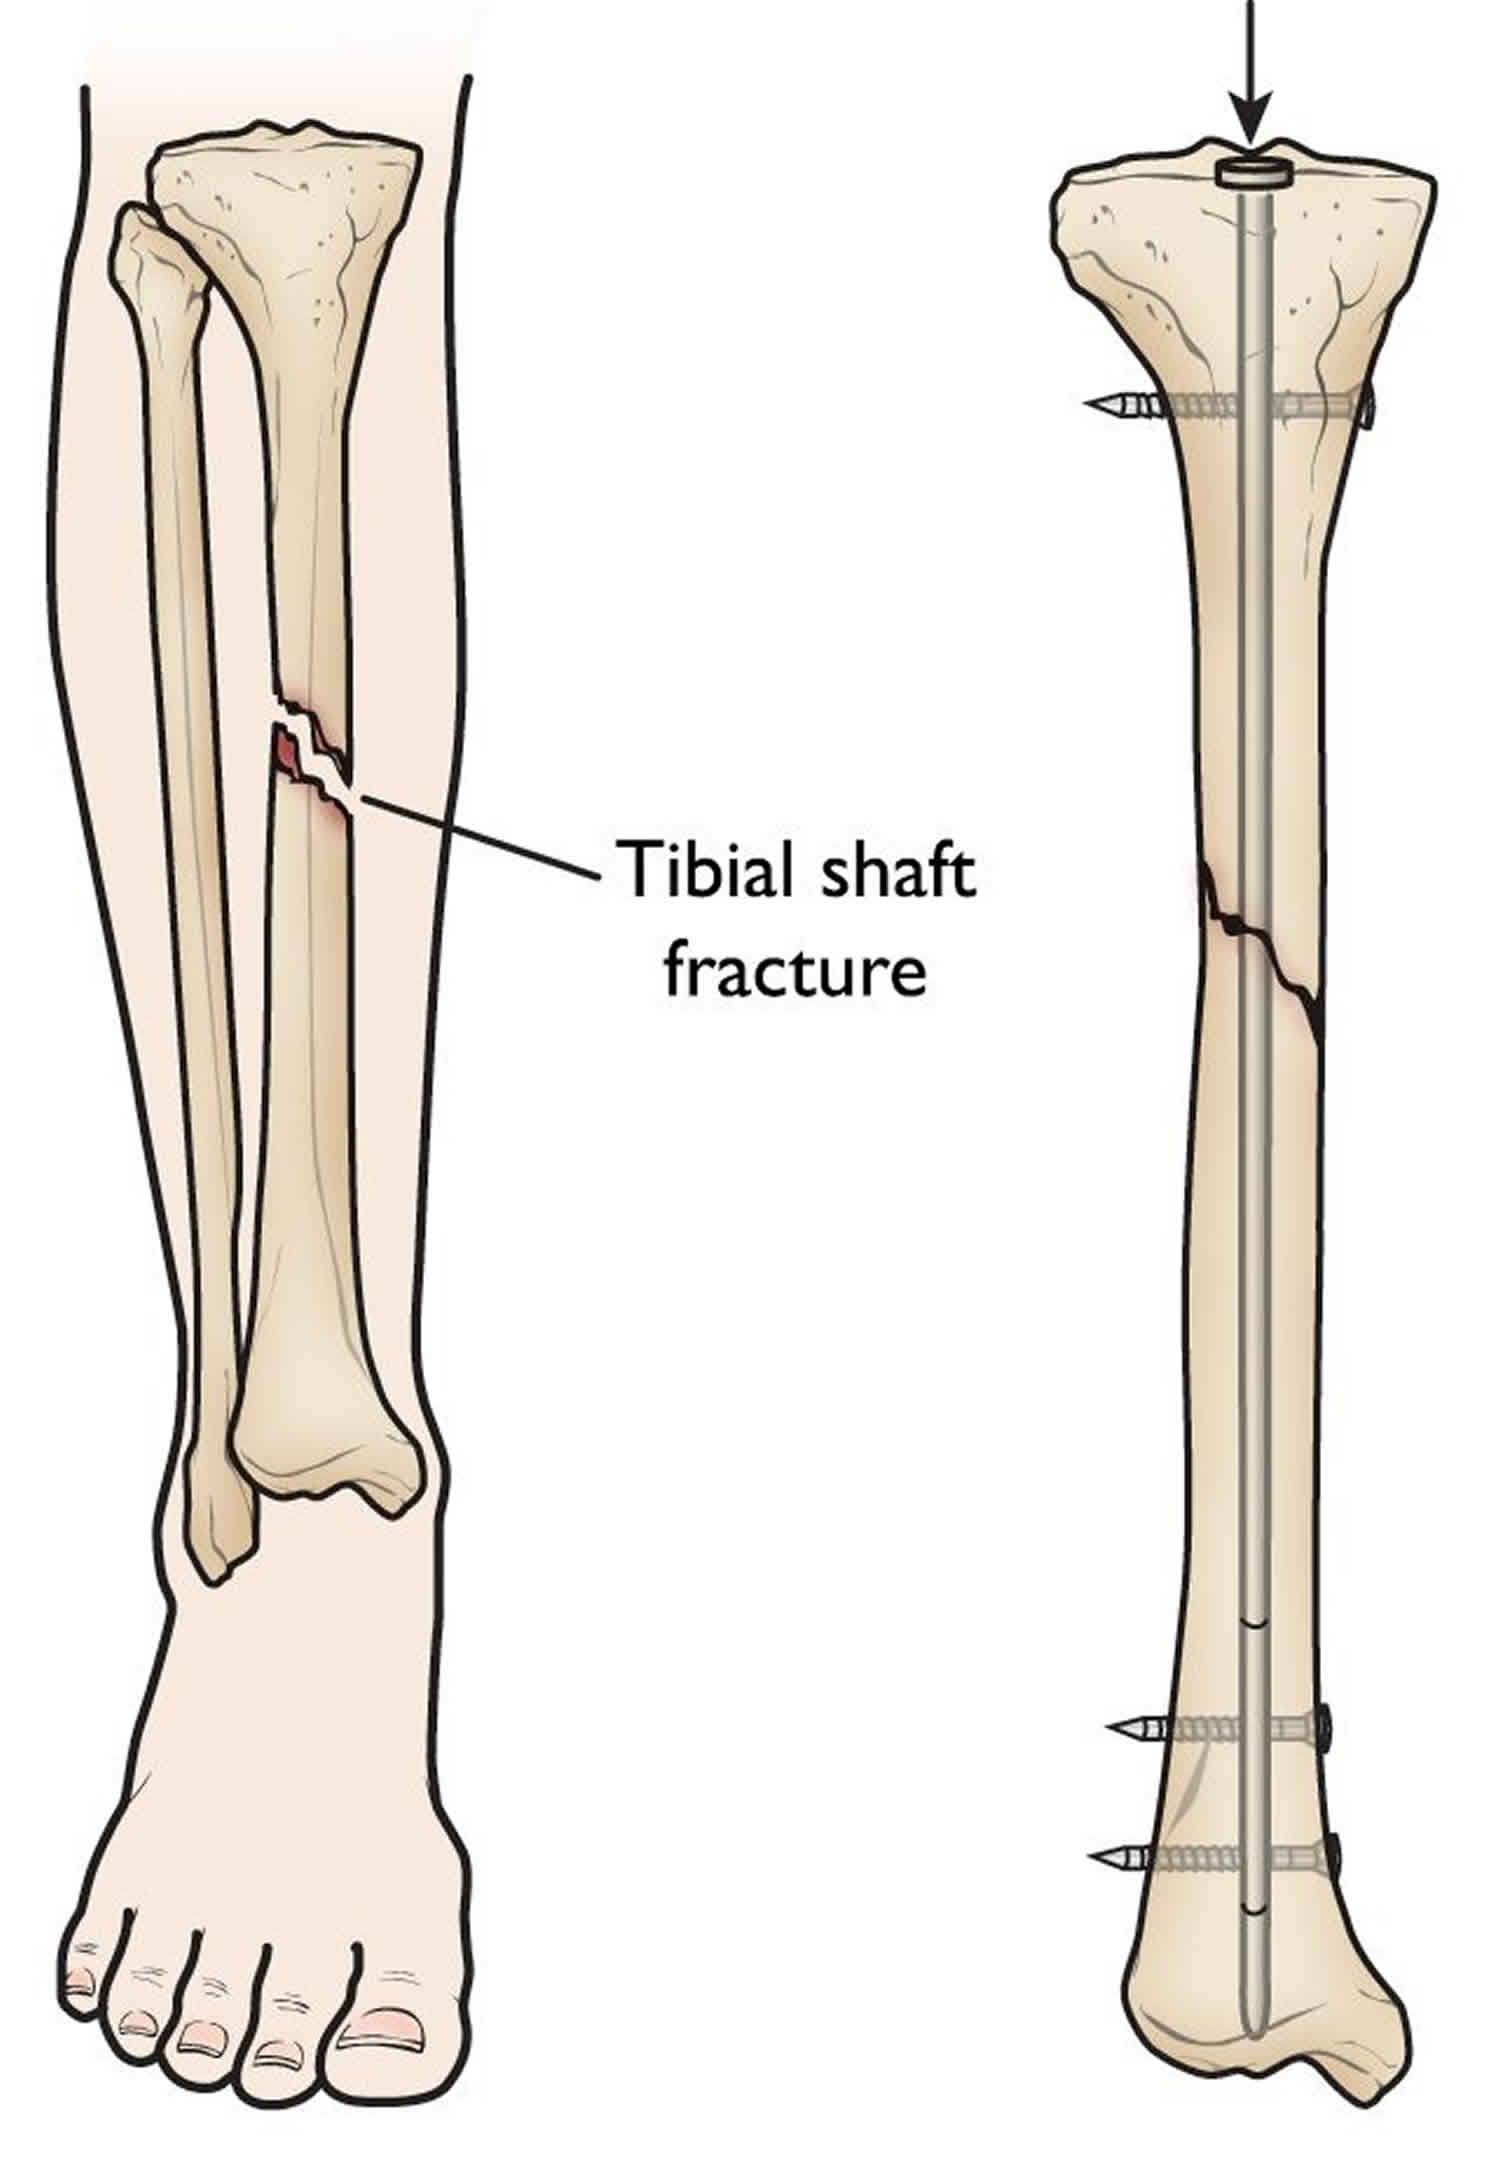

Перелом большой берцовой кости - серьезное повреждение, сопровождающееся болезненными ощущениями и нарушением функции ноги. На этой странице вы найдете много фотографий, позволяющих вам более детально изучить эту травму.

Интрамедуллярный остеосинтез

Здесь представлены медицинские изображения переломов большой берцовой кости, сделанные врачами в процессе диагностики и лечения. Вы сможете увидеть, как выглядит этот тип травмы на рентгеновских снимках и других медицинских изображениях.